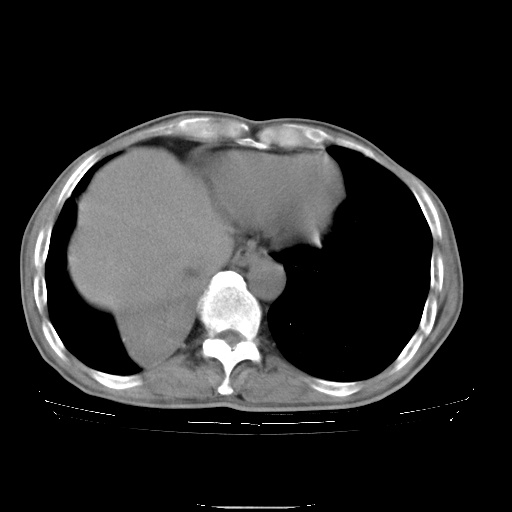

男性患者,63岁。右侧胸背部疼痛2月,加重一周。

考虑:右肺中央型肺癌并右肺下叶不张;两肺尖继发性肺结核。

考虑右中心型肺癌并右下肺不张,肺及纵隔,左肋骨转移。

右肺下叶中心性肺癌并纵隔淋巴结转移,左侧肋骨转移。双肺上叶继发性结核表现。

1)右肺下叶中心性肺癌并纵隔淋巴结转移,两肺转移,左侧肋骨转移。2)双肺上叶继发性结核。

右肺下叶中心性肺癌并纵隔淋巴结及两肺、左侧肋骨转移。双肺上叶继发性结核表现。